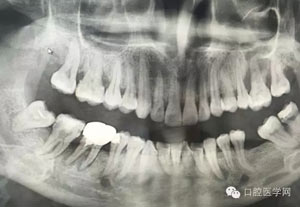

病例2:364647中齲的樹脂充填,現(xiàn)在樹脂的充填材料非常之多,有些時候,我們感覺有了好的材料我們就可以做出好的修復(fù),可是這是在我們有扎實的基本功的基礎(chǔ)上的,我們可以沒有那么好的樹脂,那么多的顏色選擇,修復(fù)的那么的逼真,但是我們至少要恢復(fù)患者牙齒的功能,將腐質(zhì)去除干凈,薄壁弱尖消除掉,選擇好適應(yīng)癥,給患者以盡可能好的修復(fù)。